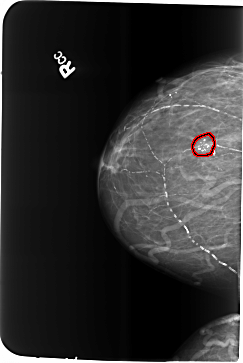

B_3481_1.RIGHT_CC

FILE: B_3481_1.RIGHT_CC.OVERLAY

TOTAL_ABNORMALITIES 1

ABNORMALITY 1

LESION_TYPE CALCIFICATION TYPE COARSE-PLEOMORPHIC DISTRIBUTION CLUSTERED

ASSESSMENT 2

SUBTLETY 5

PATHOLOGY BENIGN

TOTAL_OUTLINES 1

BOUNDARY